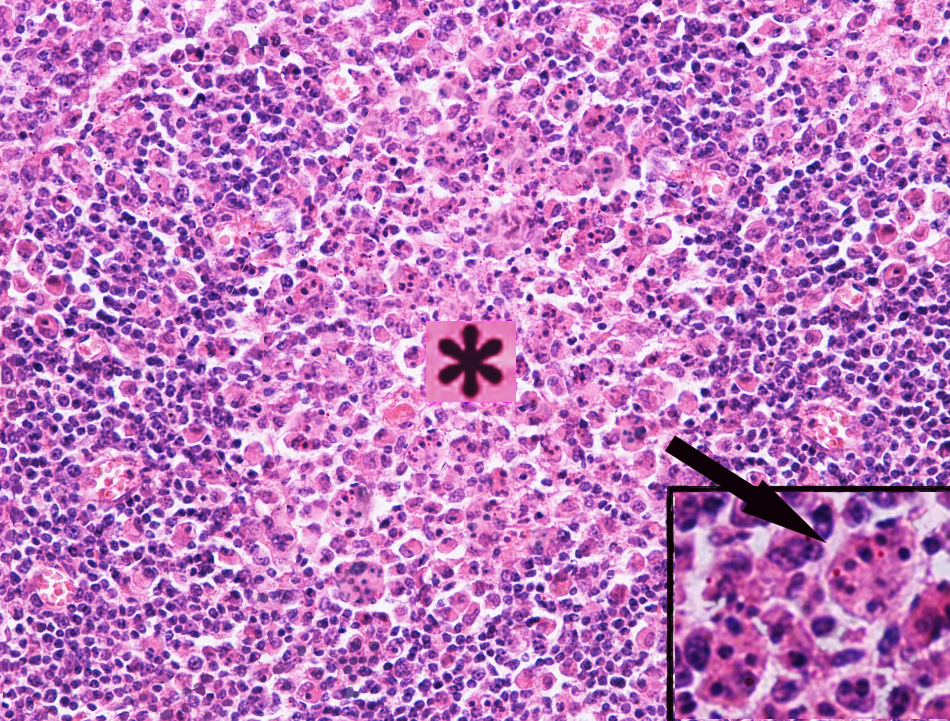

3.肠伤寒